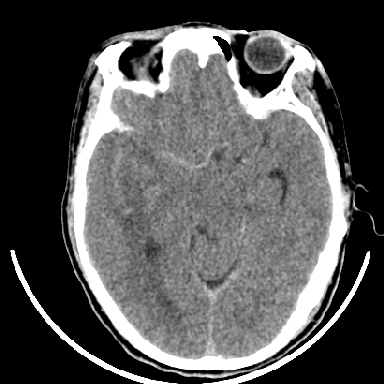

标题: CT6056:脑出血(血管畸形?) [打印本页]

标题: CT6056:脑出血(血管畸形?)

m 40突发头痛左侧偏瘫3小时

支持右侧基底节脑出血

右侧基底节区脑出血.

支持右侧基底节区(主要为外囊区)原发性脑出血。

支持右侧基底节区(主要为外囊区)原发性脑出血----有无血管畸形及动脉瘤或说出血原因待查

但脑出血早期做增强是不是有点太冒险了?

术中抽出40ml陈旧血液,血肿底部似见一条索血管影